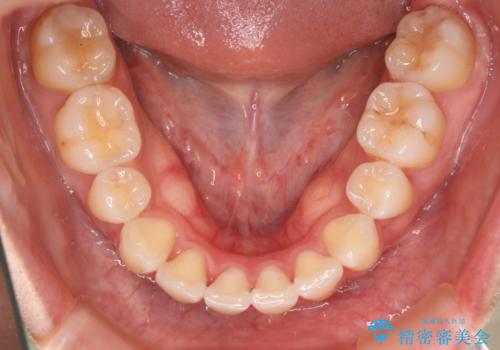

- 治療計画

- 歯のガタつきと出っ歯感を治したいとの主訴でご来院され、ハーフリンガル装置を希望なさったため、検査を行ったうえで上下左右4番目の歯を抜歯し歯列を内側に引っ込めつつ叢生の改善を行うこととなりました。